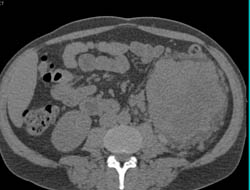

Transitional Cell Cancer (TCC) of Right Kidney Involves the Renal Vein and IVC